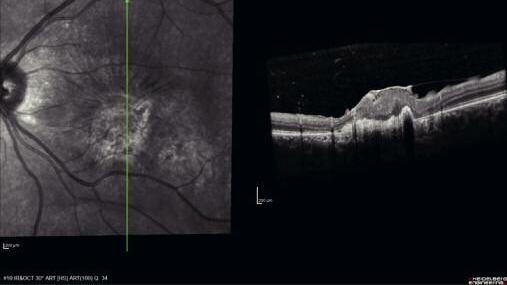

271 Fibrosi maculare post-esplosione: case report di un militare sopravvissuto

M a c u l a r f i b r o s i s a f t e r b o m b e x p l o s i o n : a c a s e r e p o r t a b o u t a survived military man

I traumi da scoppio del bulbo oculare comportano generalmente conseguenze irreversibili per la vista I meccanismi fisiopatogenetici dei danni da onda d’urto sono descritti nel caso riportato dagli autori che forniscono anche i lineamenti di terapia e riabilitazione